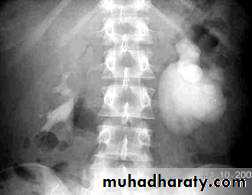

US: pre- and post-natal.IV Urography

VUR is classified into 5 grades depending on the severity of reflux and the associated dilatation of the renal system.